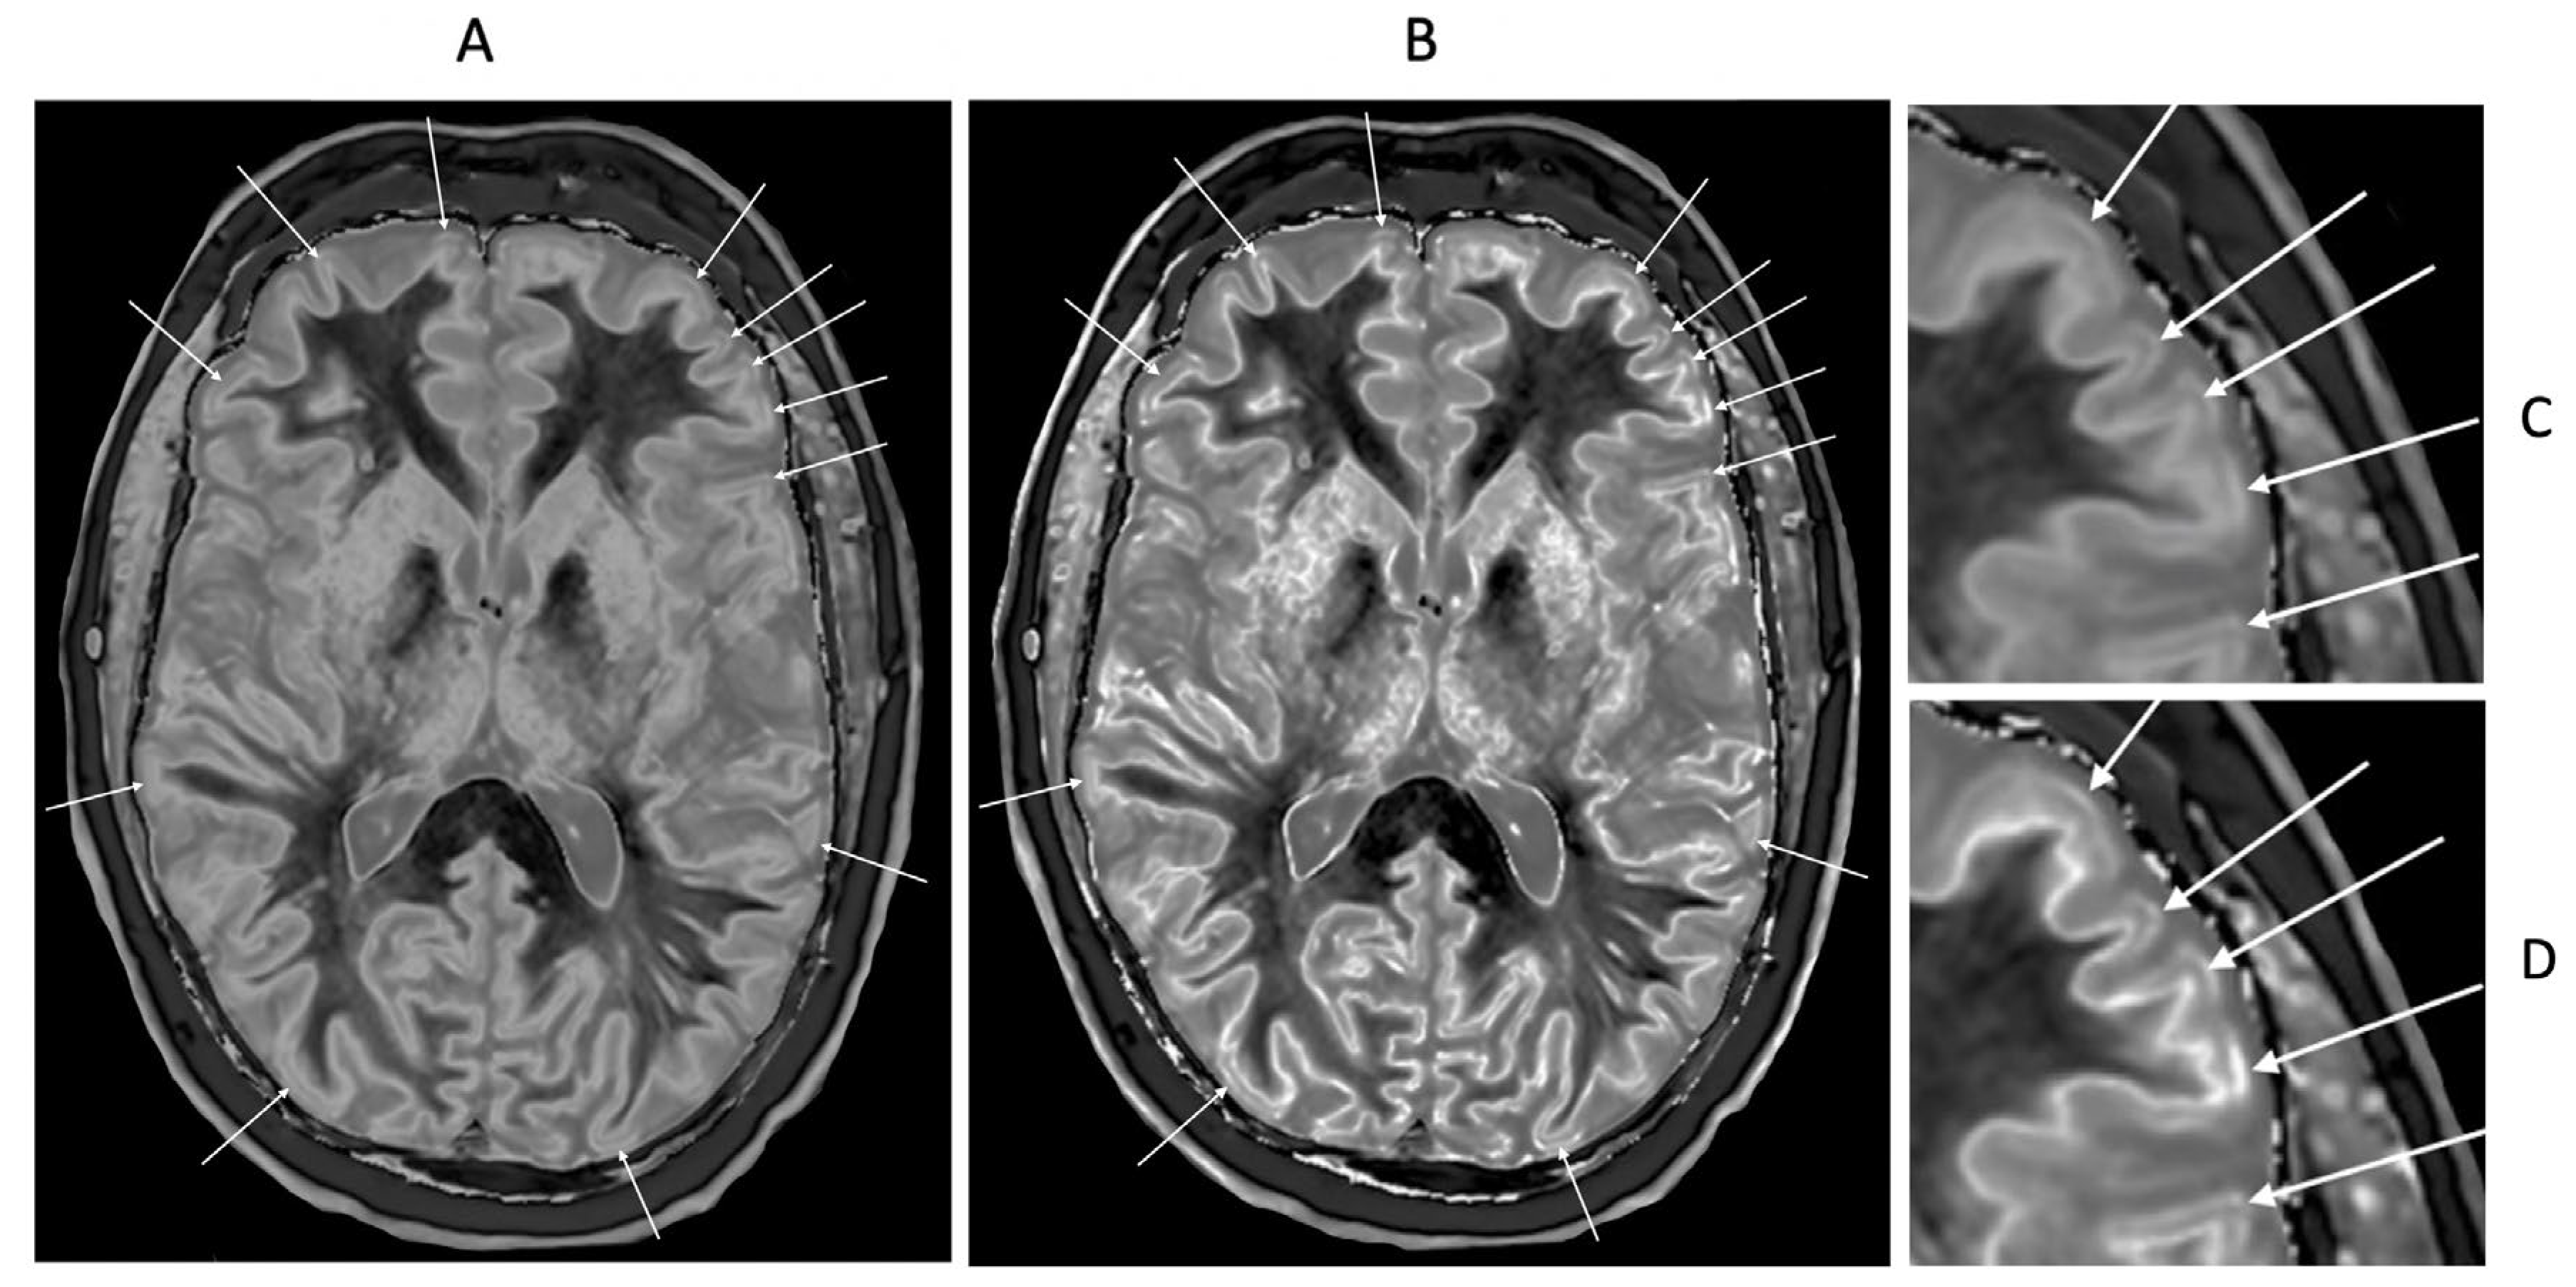

Figure 13.

Normal control (A) and patient with mTBI (B) showing a whiteout sign and grayout signs (narrow mD dSIR images). The normal control shows the heads of the caudate nuclei with higher signal than the adjacent CSF. Contrast is also seen between the cortex and CSF. In (B), the patient shows a whiteout sign. There are grayout signs in the thalami and putamina. In addition, contrast between the heads of the caudate nuclei and CSF is lost and there is little or no contrast between cortex and CSF which are isointense. These are also grayout signs. No abnormality was seen on the T2-FLAIR images in the normal control or patient.